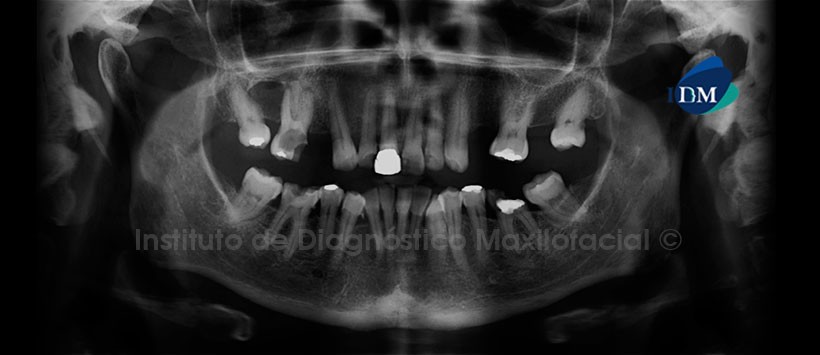

En la evaluación panorámica, se aprecian la ausencia de múltiples piezas dentarias, corona protésica en la pieza 11, lesión cariosa en las piezas 21, 22 y 46 con aparente compromiso pulpar, material de restauración en las piezas 26, 35 y 35, remanente radicular de la pieza 36 y presencia de placa dental mineralizada en zona cervical de las piezas 44 y 46. Siendo dos hallazgos lo más resaltante de esta imagen, la primera es la presencia de lesión cariosa amplia de la pieza 16 con compromiso pulpar, ocasionado la presencia de lesiones periapicales con osteítis circundante y segundo, la presencia de una imagen radiolucida en zona proximal de las piezas 16 y 18 de limites definidos parcialmente corticalizado ocasionando el borramiento de la lámina dura de ambas piezas. (Figura 2)